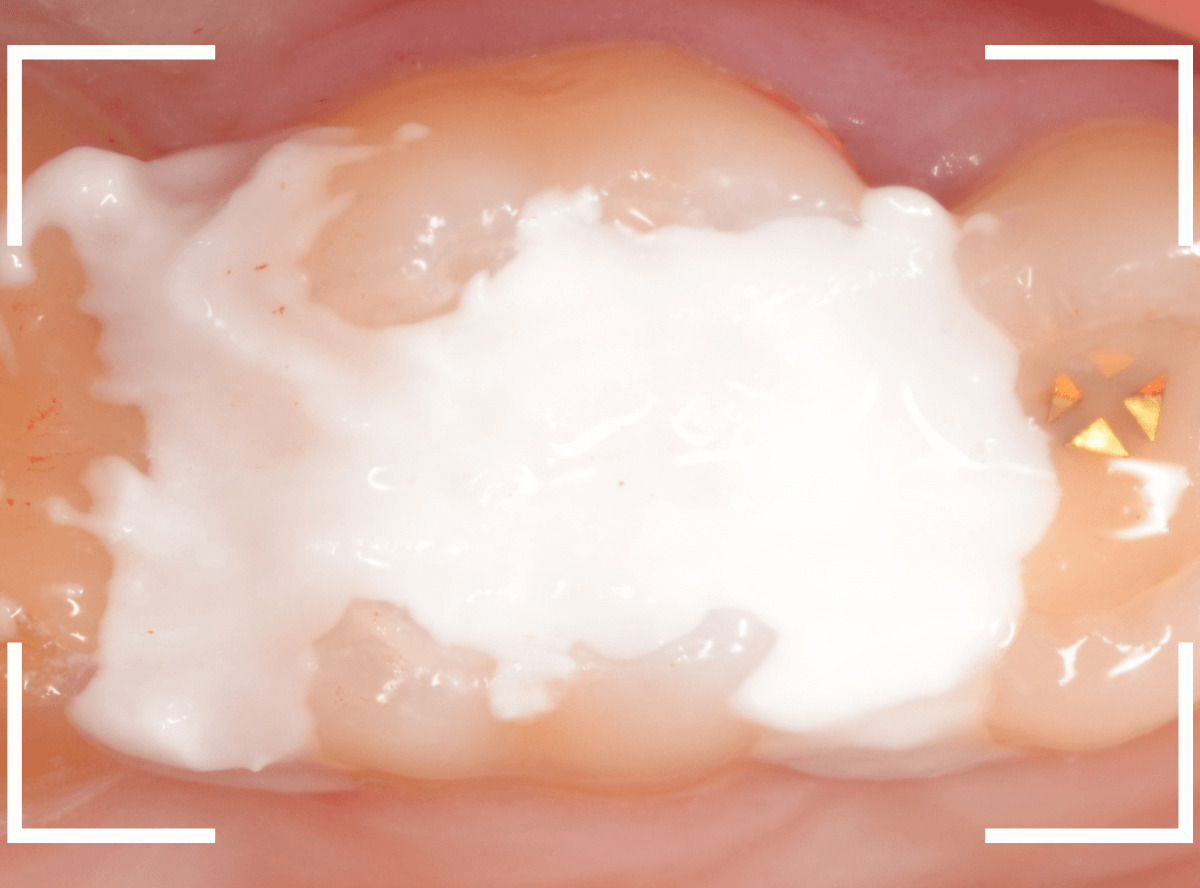

Case.5 上の一番奥の部分が深い虫歯!2

こちらも上の奥歯の奥側が虫歯になってしまった患者さんです。

本人に自覚症状はないようですが、一見して虫歯が大きそうだな、と思いました(><)

青い線が歯の神経、赤い線が虫歯です。

以前にレジン治療をした中で虫歯が進行してしまい、かなり神経に近くなってしまっていると思われます。

麻酔をして、レジンの部分を全部除去したところです。

見えづらいですが、まだ虫歯が残っているのがわかります(黒い部分)。

虫歯を全部除去したところです。

歯の1/3くらいは削る必要のある大きな虫歯でした。

神経に近い虫歯でしたので、お薬をつめてしばらく経過観察になります。